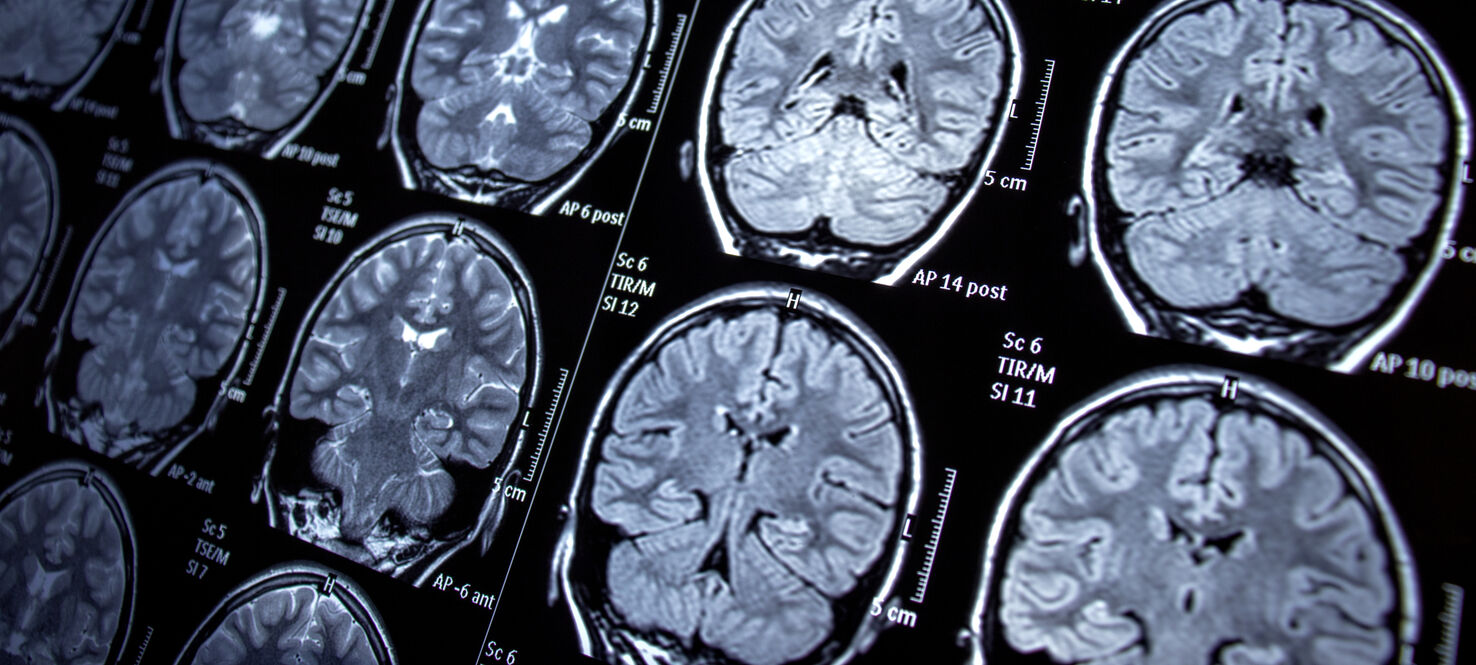

Researchers examined 101 asymptomatic patients diagnosed with stage 4 breast cancer, including triple-negative, HER2-positive and hormone receptor-positive/HER2-negative breast cancer. These patients underwent MRI scans to check for brain metastasis, with a follow-up MRI six months later if the initial scan showed no signs of cancer spread.

Of the patients who completed the initial MRI, 14% had brain metastasis. The rates by subtype were:

- 18% in triple-negative breast cancer

- 15% in HER2-positive breast cancer

- 10% in hormone receptor-positive/HER2-negative breast cancer

After the second MRI, the number of patients with brain metastasis grew to about 25% in each subtype. Following diagnosis, patients went on to receive early treatment for their brain metastases, including changes in systemic therapy and local therapies.